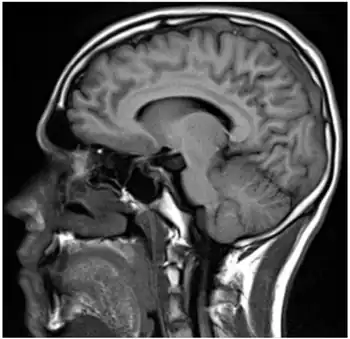

| Sagital-Prothrombin G20210A as cause of cerebral venous thrombosis | |